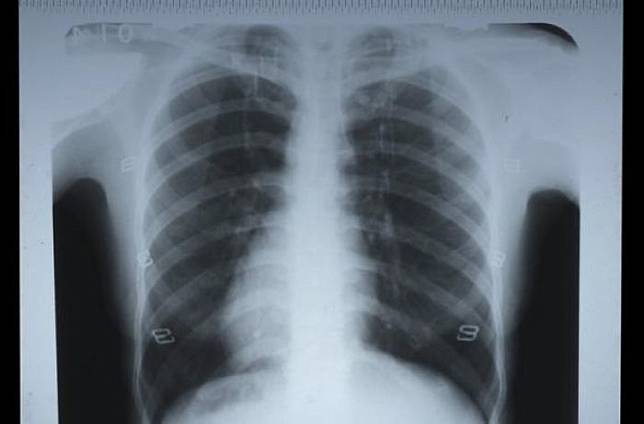

BeritaMalam – Seorang pria berusia 47 tahun yang tidak disebutkan namanya dirujuk ke klinik pernapasan.

Pria asal Preston, Lancashire, Inggris, ini mengeluhkan batuk lendir kuning dan merasa tidak enak badan selama lebih dari satu tahun.

Saat itu, petugas medis mengira ia menderita kanker paru-paru.

Karena ia baru saja menderita pneumonia dan pernah menjadi perokok jangka panjang.

Namun setelah bronkoskopi, tindakan medis yang bertujuan untuk melihat trakea dan bronkus, para petugas medis menyadari bahwa ‘sesuatu’ di paru-parunya itu bukanlah tumor.